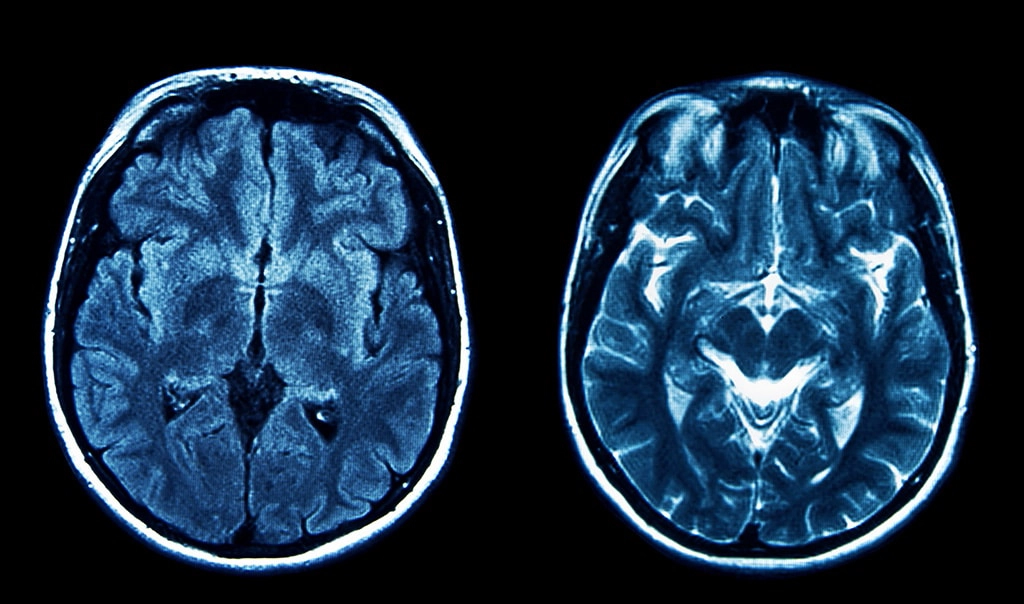

My Program

I wanted to combine my interest in this topic with my love for programming, which led to the idea of making a tumor detecting program. I coded my project in Python and used PyTorch and timm libraries for training. I imported about 5000 labeled images of meningiomas, gliomas, pituitary, and normal MRI scans. In order to train the model I used a pre-trained model and supervised learning. Supervised learning is when we import images into a model with labels on the correct description. In my case, my images had the correct type of tumor labeled. These images are given to the model and the model's job is to guess the type of tumor in the image. After the guess, the model gets the correct answer from the label. Going forward the model adjusts its answers until it has a high accuracy or it runs through all of the test images.